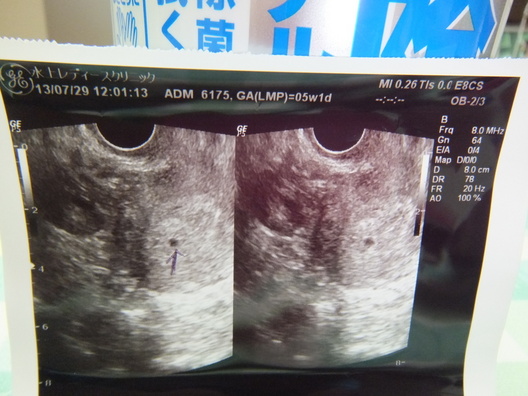

5W1D 胎嚢確認できました(^-^)

エコーが映し出され、先生が『ここに赤ちゃんいるよ、小さいけど可愛い胎嚢だよ。』そう、言われ恐る恐るモニターを見るととても小さいけれど可愛い胎嚢が

確認できて、感激で泣きそうになりました。

そのエコー写真がこちらです。

2枚並べてあるエコーをもらいました。同じ写真ですが、おそらく角度が少し

違うのだと思われます。